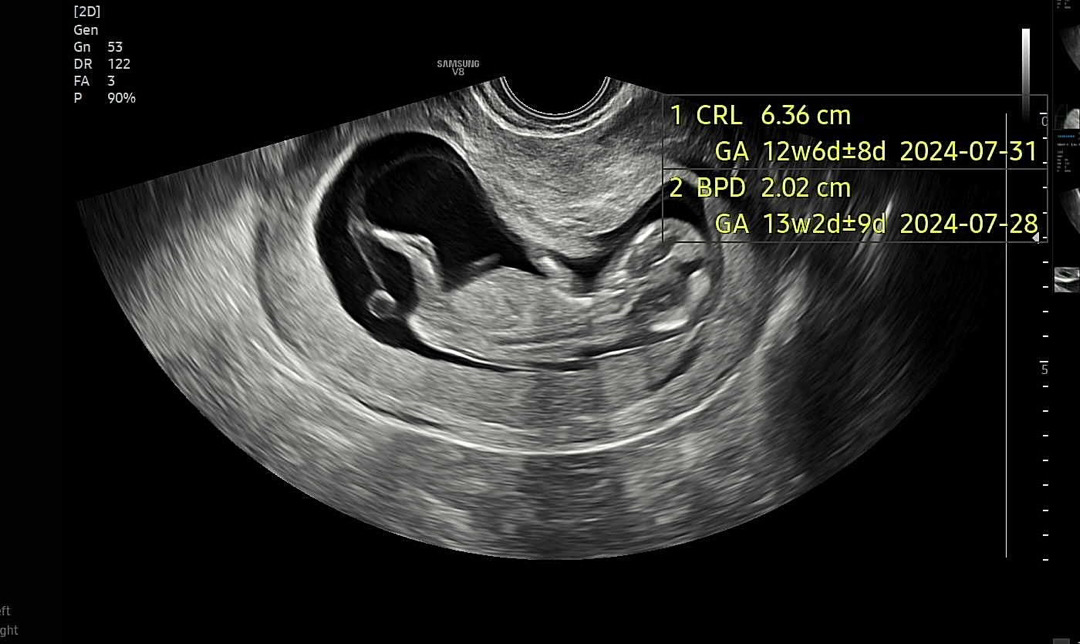

12주차 아기 집이 좁아보여요 초음파봐주세영

성별도 궁금하고.. 다른분들 초음파도 궁금해요~

홀 다리가 엄청 긴 거 같아요!!! 롱다리

초음파 화질 정말 좋네요! 저도 비슷한거 같아요 ㅎ 비좁은 아기집 ㅎ

저도 딱 저래요~ 좀 좁아보여서 여쭤보니 단면으로 보여서 그러거라구 괜찮다하시더라구용😖ㅋㅋ